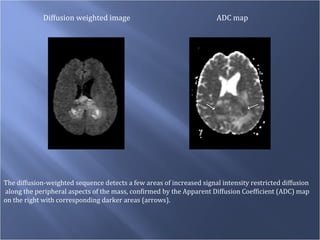

Diffusion weighted image ADC map The diffusion-weighted sequence detects a few areas of increased signal intensity restricted diffusion along the peripheral aspects of the mass, confirmed by the Apparent Diffusion Coefficient (ADC) map  on the right with corresponding darker areas (arrows).

Diffusion weighted imageADC map The diffusion-weighted sequence detects a few areas of increased signal intensity restricted diffusion along the peripheral aspects of the mass, confirmed by the Apparent Diffusion Coefficient (ADC) map on the right with corresponding darker areas (arrows).